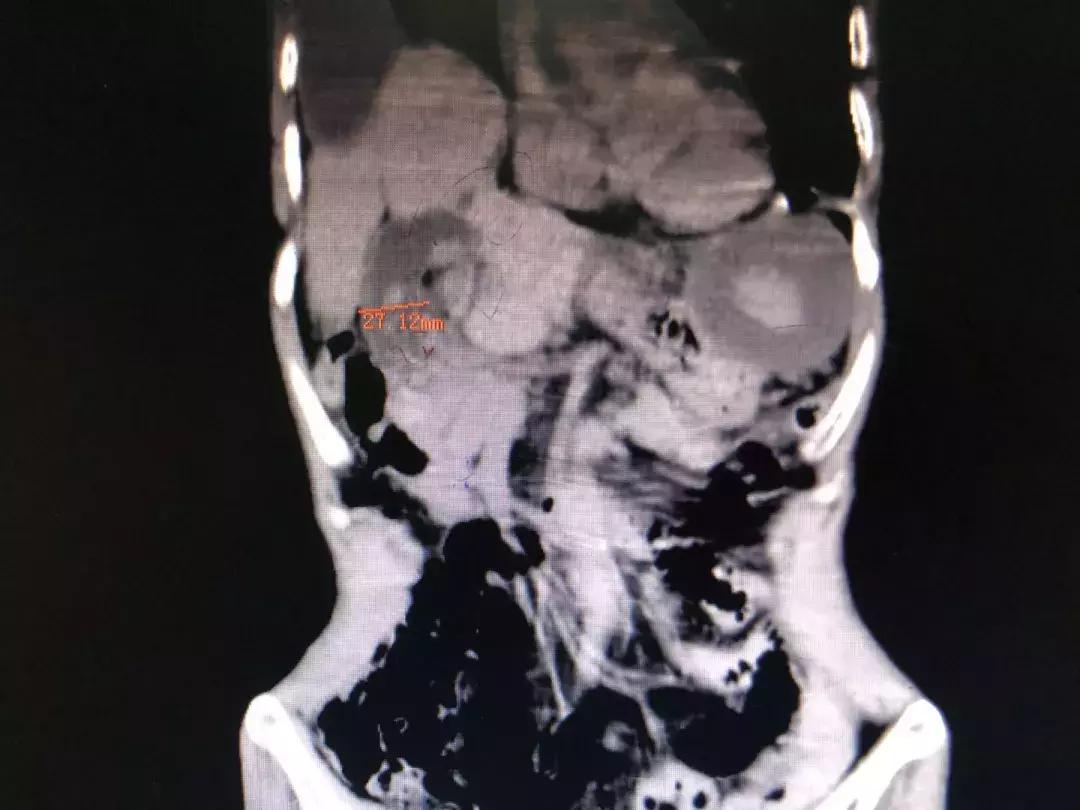

术前影像资料显示,胆管直径达27mm,为正常的四倍。

右侧膈肌缺如,部分腹腔脏器上移至胸腔内。